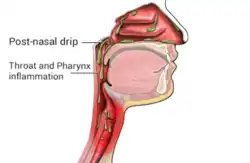

Post-nasal drip (PND), also known as upper airway cough syndrome (UACS), occurs when excessive mucus is produced by the nasal mucosa. The excess mucus accumulates in the back of the nose, and eventually in the throat once it drips down the back of the throat. It can be caused by rhinitis, sinusitis, gastroesophageal reflux disease (GERD), or by a disorder of swallowing (such as an esophageal motility disorder). Other causes can be allergy, cold, flu, and side effects from medications.

PND may present itself through the constant presence of discomfort in the upper airways. It is classically described as the sensation of a substance "dripping down the throat" and may also present with rhinorrhea, constant throat clearing, and cough, although its symptoms can be very nonspecific.[2] PND is one of the most common etiologies for chronic cough, defined as a cough persisting beyond 8 weeks.[3]

Post-nasal drip can be a cause of laryngeal inflammation and hyperresponsiveness, leading to symptoms of vocal cord dysfunction.[4][5][6]

The exact mechanism of PND depends on its etiology, but usually involves increased production of mucus from the nasal mucosa. In addition to providing sense of smell, the nasal cavity serves to filter and regulate the temperature and humidity of inspired air.[7] The nasal mucosa can produce secretions, or mucus, that provides lubrication and protection for the nasal cavity. This mucus production is activated by the autonomic nervous system; specifically, cholinergic neuropeptides are responsible for increasing mucus production.[7] Excess mucus can drain posteriorly into the upper and lower airways, which, along with other physical and chemical irritants, can activate receptors in the respiratory tract that results in a protective physiological cough.[9] In some patients, mucus recirculation between natural and accessory ostia has been described as a mechanism that perpetuates post-nasal drip and chronic rhinosinusitis.[10]